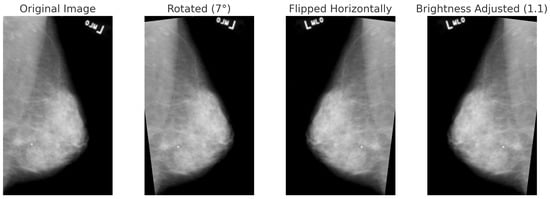

The BUSI dataset consists of 830 breast ultrasound images collected from 600 female patients aged between 25 and 75 years. These images are classified into three diagnostic categories: normal, benign, and malignant (see Figure 3). Additionally, the dataset includes ground truth segmentation masks that aid in accurate lesion delineation. Each image is saved in PNG format with a resolution of 500 × 500 pixels, ensuring consistency for preprocessing and analysis. Unlike histopathological imaging, ultrasound imaging poses challenges such as low signal-to-noise ratios and greater variability.

For BreakHis, extensive geometric (rotation ± 20°, flips) and photometric (zoom, brightness) transformations were applied to reflect slide orientation variability and staining inconsistencies. BUSI employed elastic deformation, speckle noise, and contrast adjustment to mimic tissue distortion and signal artifacts. INbreast received conservative adjustments to enhance tissue visibility without losing diagnostic fidelity. CBIS-DDSM used mild rotation, flipping, and brightness changes, maintaining lesion structure integrity. The Combined Dataset integrated harmonized augmentations from all sources, ensuring cross-modality consistency while retaining BUSI-specific elastic transformation. The chosen values prioritize generalization while preventing excessive transformations that could alter pathological features or diminish diagnostic relevance. Figure 6, Figure 7, Figure 8 and Figure 9 illustrate sample images from each dataset after the application of these data augmentation techniques.